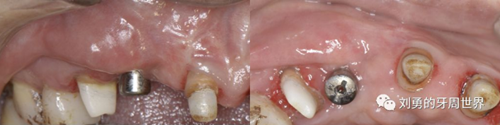

比如strip技術(shù),如下圖:

上圖中,種植體唇側(cè)缺乏附著齦,從上腭取瓣,常規(guī)做法:取長(zhǎng)而寬的齦瓣,這樣供區(qū)面積大,術(shù)后疼痛重。

為了減少痛感,從雙側(cè)上腭取多條長(zhǎng)而窄的齦瓣進(jìn)行移植,這樣每個(gè)供區(qū)的傷口都比較窄,可以減少術(shù)后的痛感。

可見右上前牙植體頰側(cè)無附著齦

為了減少取瓣大小,從上腭取厚一點(diǎn)的齦瓣,然后用刀片平行于表皮表面將齦瓣片切成兩個(gè)厚度一致的齦瓣,然后進(jìn)行移植,這樣切成的兩個(gè)齦瓣一個(gè)有表皮,一個(gè)沒有表皮是單純的結(jié)締組織。如此的片切可以使齦瓣變成雙倍的大小使用,減少了供區(qū)的取瓣面積。